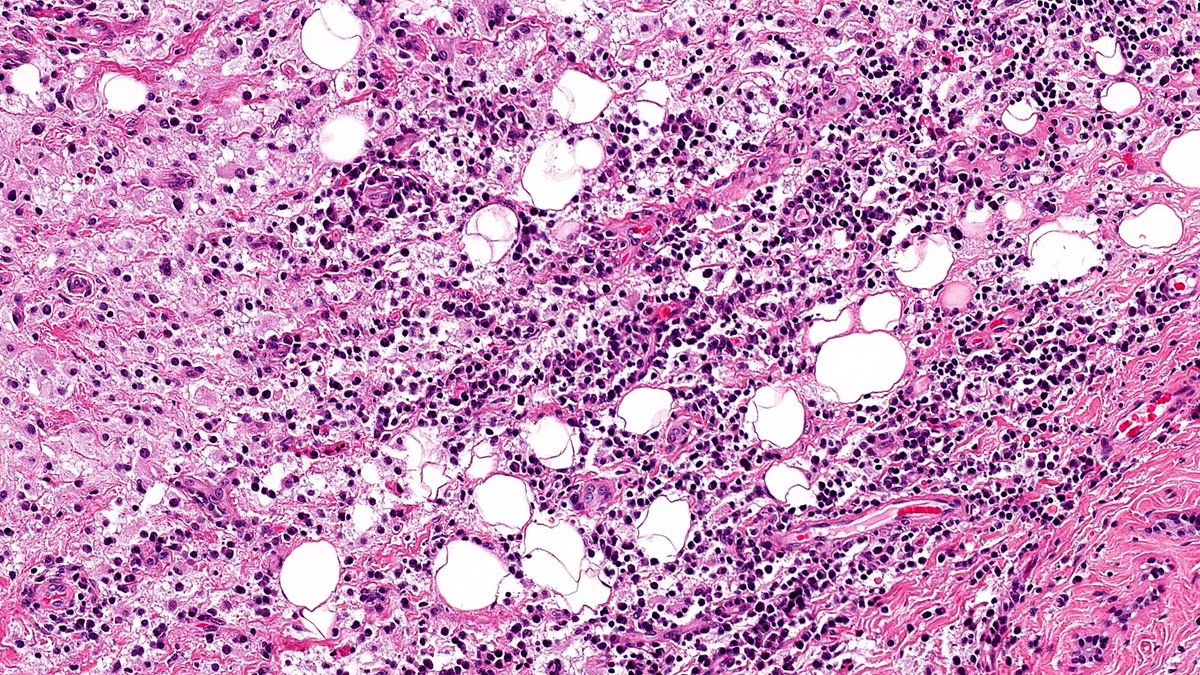

61F never smoker, large axillary mass with widespread Mets including multiple brain Mets. CD10 strongly positive (shown). Mutations in p53, RB1, and TERT. DDx? Stain suggestions? #pathx #pathtwitter #cnspath #neuropath #neuropathology

PeterKobalka's tweet image. 61F never smoker, large axillary mass with widespread Mets including multiple brain Mets.   CD10 strongly positive (shown). Mutations in p53, RB1, and TERT.  DDx?  Stain suggestions?  #pathx #pathtwitter #cnspath #neuropath #neuropathology